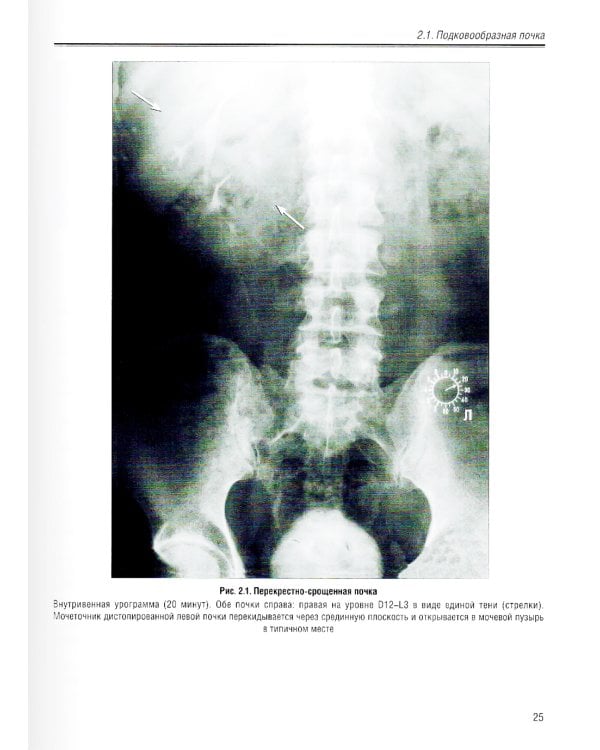

В учебном пособии изложена нормальная лучевая анатомия почек, мочеточников и мочевого пузыря по данным рентгенологического исследования, КТ, МРТ и УЗИ. Приведено описание лучевой семиотики наиболее часто встречающихся заболеваний и повреждений почек, мочеточников и мочевого пузыря с представлением данных УЗИ, КТ и МРТ. Даются рекомендации по тактике лучевого исследования, приводится дифференциальная диагностика. Рассматриваются вопросы этиологии, патогенеза, морфологии и клинические проявления заболеваний. Предназначено для ординаторов, обучающихся по специальностям: 31.08.08 - «Радиология»; 31.08.09 - «Рентгенология»; 31.08.11 - «Ультразвуковая диагностика», а также врачей смежных специальностей. Учебное пособие может быть рекомендовано для подготовки в системе непрерывного медицинского образования.| Издательство | Элби |